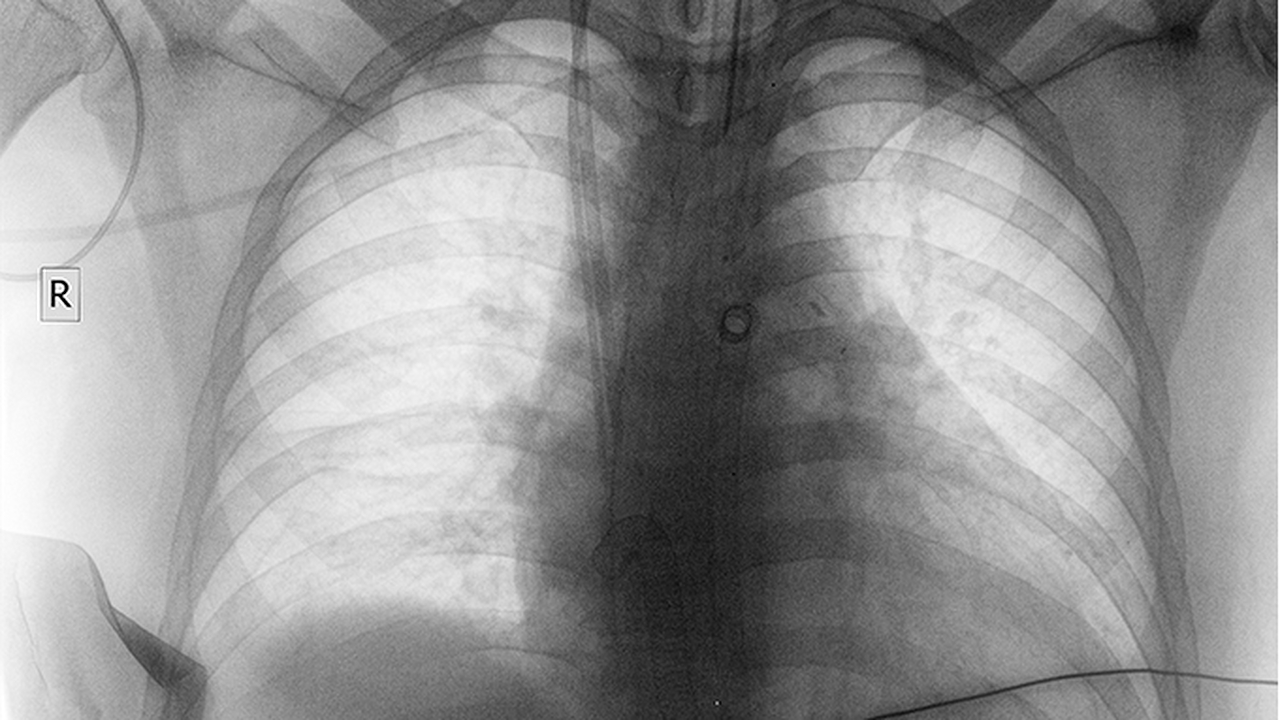

長(cháng)期吸煙者出現肺部隱痛應及時(shí)進(jìn)行胸部CT檢查,明確病因后針對性治療。日常生活中需堅持呼吸功能鍛煉,如腹式呼吸、縮唇呼吸等。保持居住環(huán)境通風(fēng)良好,避免接觸粉塵等刺激性氣體。定期進(jìn)行肺功能檢測,監測疾病進(jìn)展。若出現咯血、持續發(fā)熱等癥狀需立即就醫。